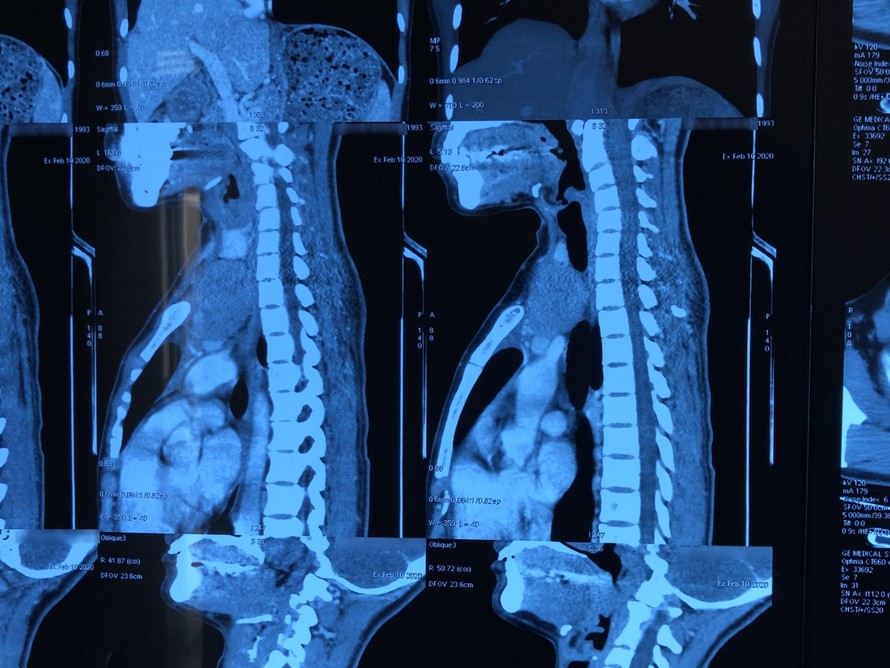

Thấy cổ to lên bất thường, chị N.T.H., sinh năm 1993, trú tại Cẩm Khê, Phú Thọ liền đến Bệnh viện Ung Bướu Hà Nội để kiểm tra. Qua thăm khám ban đầu,nghi ngờ có u giáp trái. Bệnh nhân được chỉ định chụp cắt lớp 64 dãy vùng cổ kết hợp sinh thiết kim. Kết quả giải phẫu bệnh và chẩn đoán hình ảnh xác định là u tuyến ức typ AB tại vị trí trung thất trước trên và một phần vùng cổ trái kích thước 8x5cm hay còn gọi là u tuyến ức lạc chỗ.

U tuyến ức là khối u hiếm có nguồn gốc từ các tế bào biểu mô tuyến ức. Chúng chiếm khoảng 1% các khối u ở người lớn và là khối u thường gặp nhất trong u trung thất trước. U tuyến ức lạc chỗ có nguồn gốc từ sự di chuyển bất thường của mô tuyến ức trong thời kì phôi thai. Các vị trí thường gặp nhất của u tuyến ức lạc chỗ là cổ, trung thất giữa, trung thất sau và phổi.